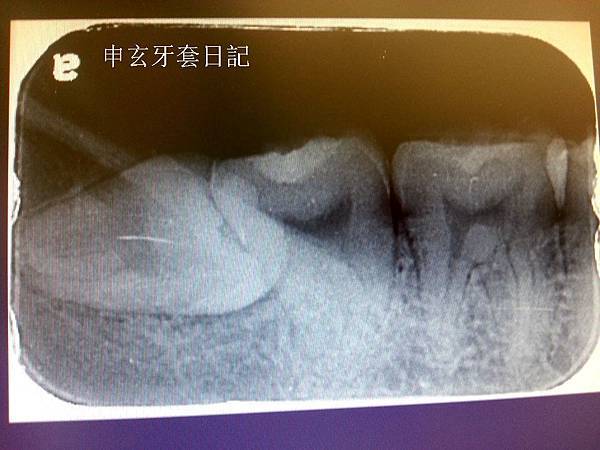

我下面的左右智齒都是最靠北的"水平智齒",水平智齒要開刀才能拔出來~

第一次拔右下的智齒,整個過程都不會痛,包括打麻醉針(因為有用表麻),

但是有夠累的,嘴巴一直張大,拔了一個多小時,因為牙齒很頑固拔不出來,

所以又切更深然後牙齒鑽碎了兩次才拔得出來,我看血都噴到醫生眼鏡上了...